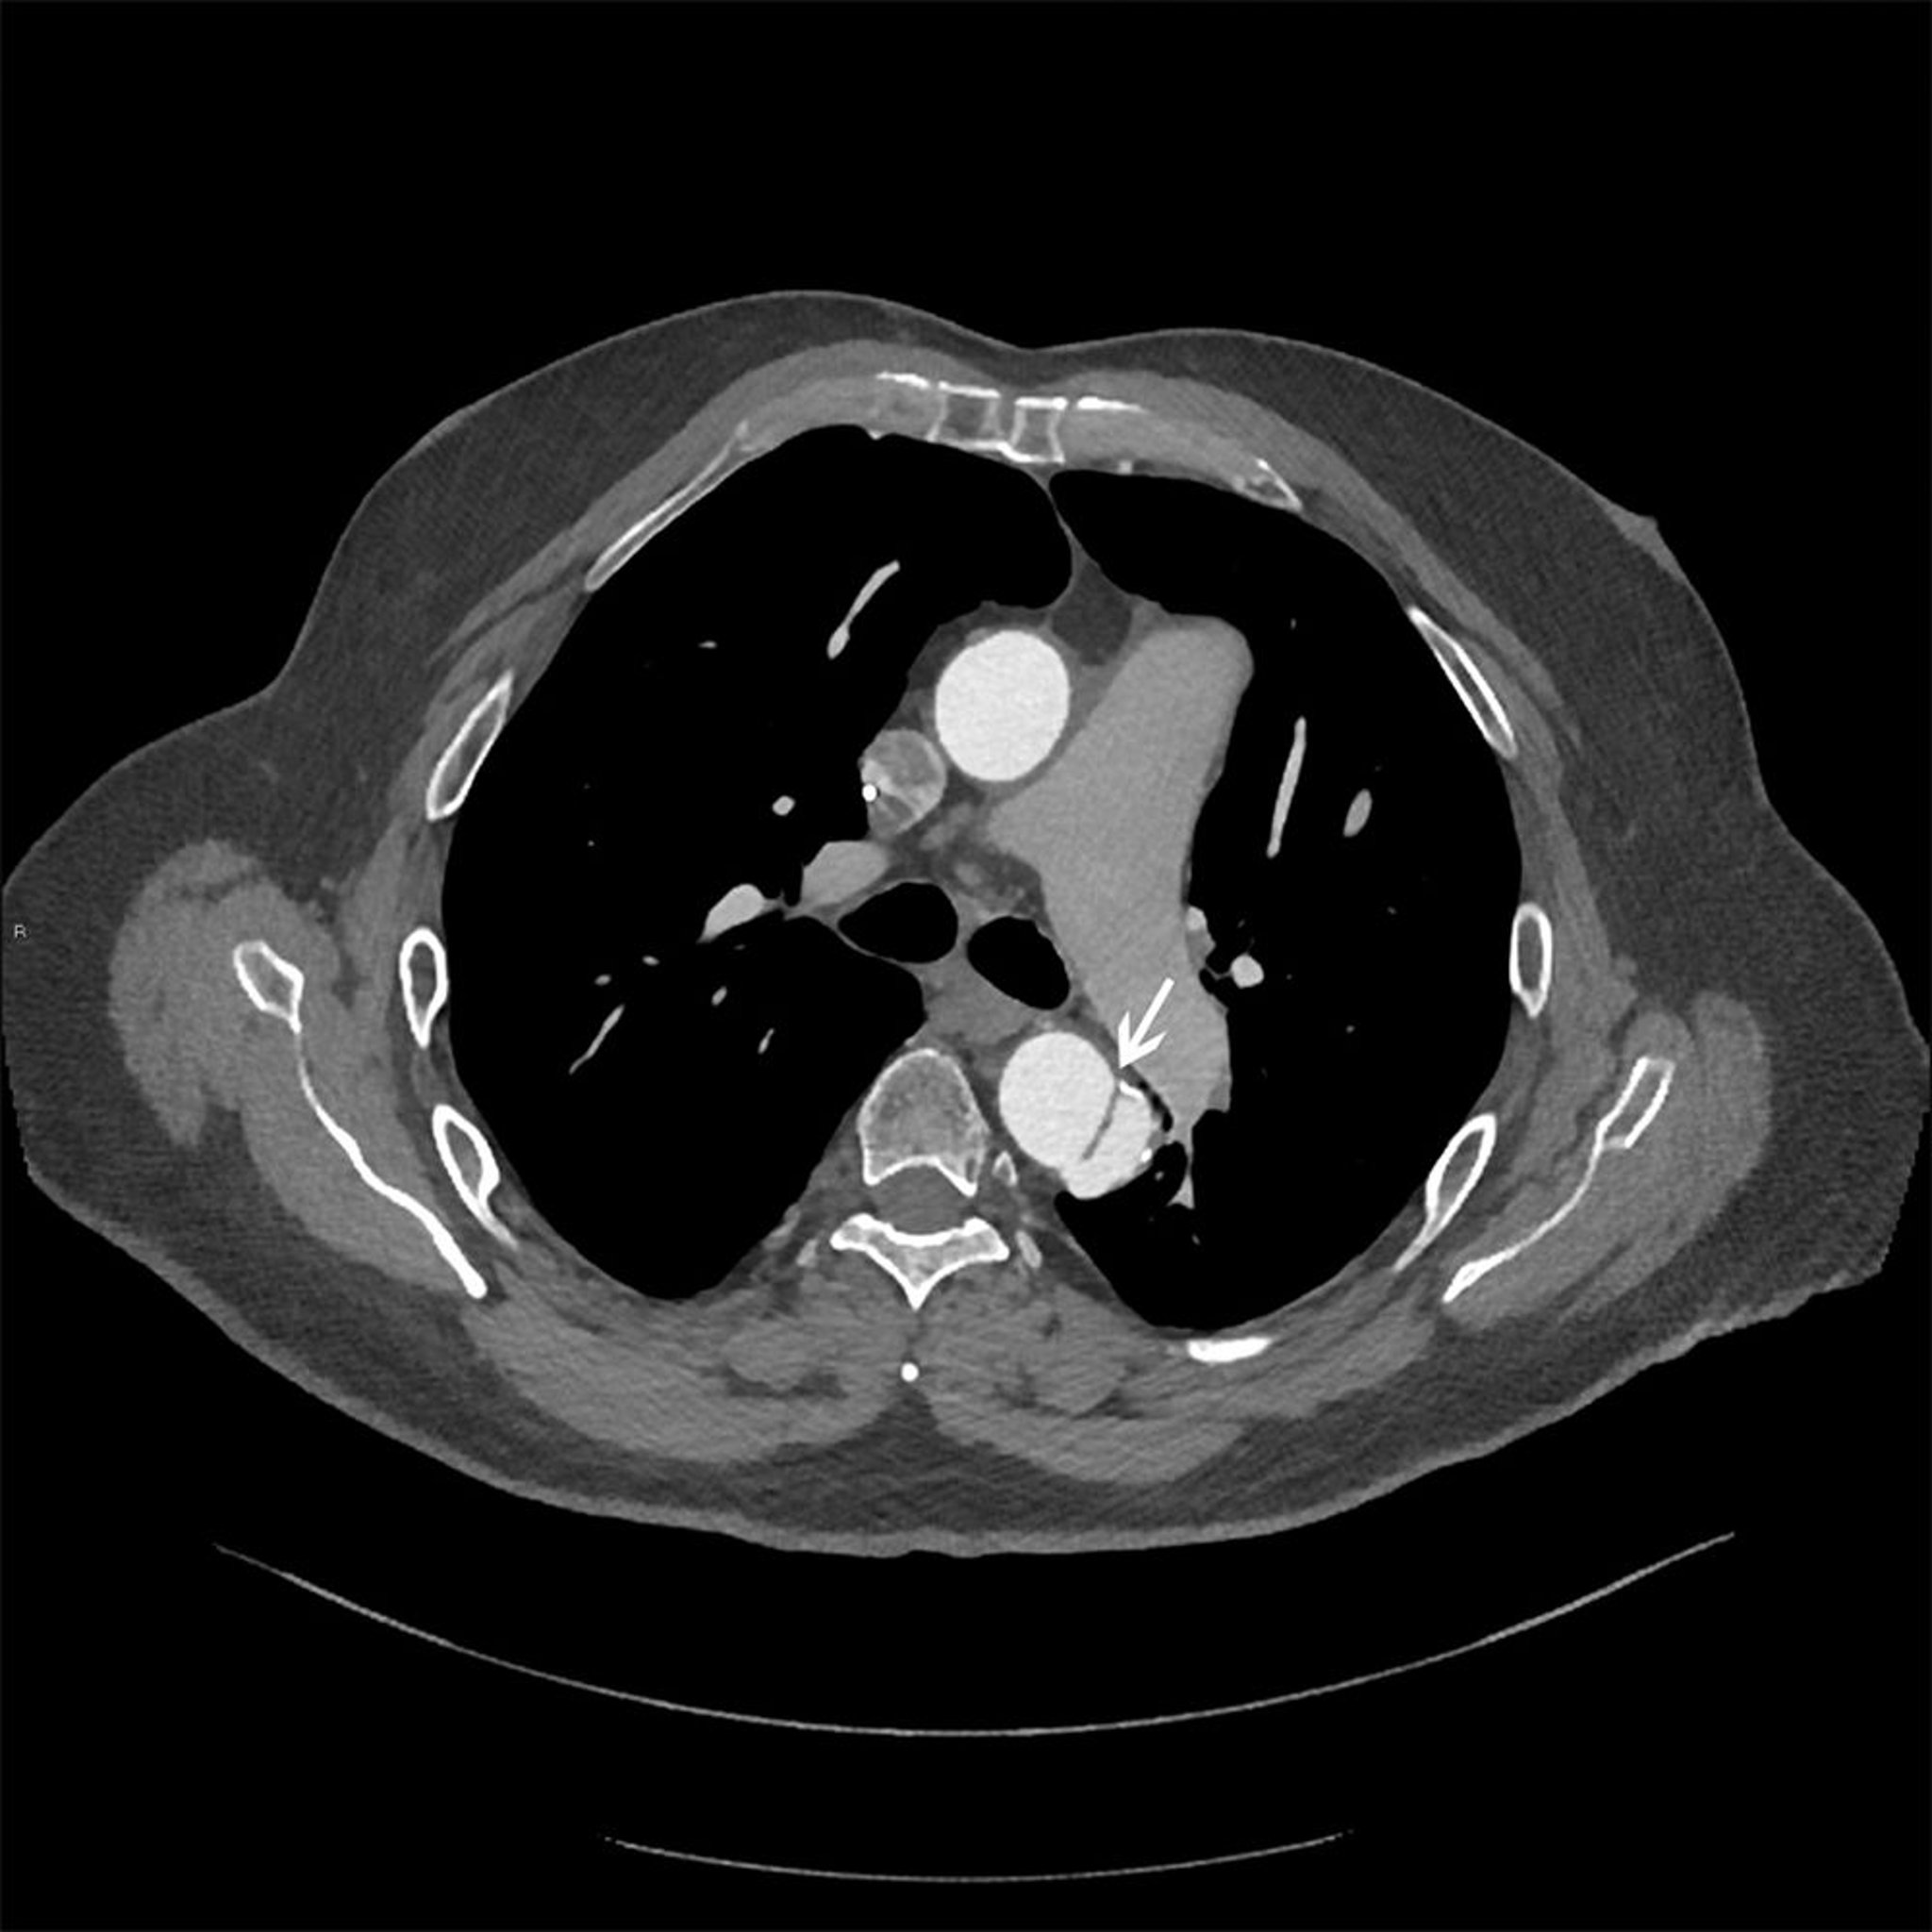

Thoracic Aortic Dissection (Stanford Type B)

Axial image of dissection flap (white arrow) in descending thoracic aorta.

© 2017 Elliot K. Fishman, MD.